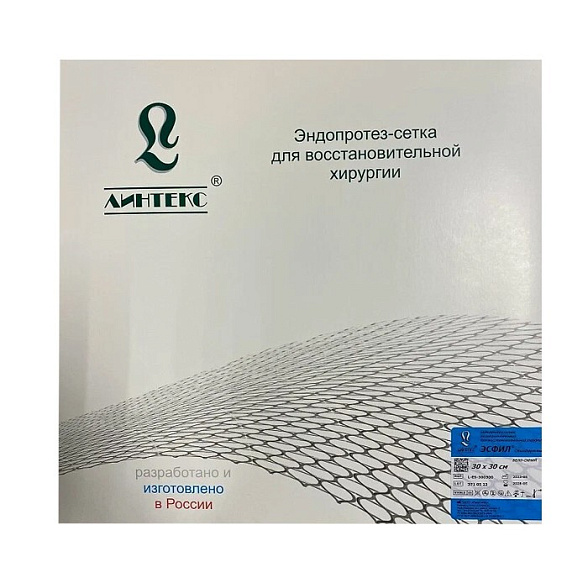

Эндопротез-сетка (сетка хирургическая) полипропиленовый для восстановительной хирургии ЭСФИЛ лёгкий, 20х15 см, Линтекс

Эндопротез-сетка полипропиленовая ЭСФИЛ лёгкий для восстановительной хирургии

Представляем вашему вниманию высокотехнологичный хирургический имплант — эндопротез-сетку полипропиленовую ЭСФИЛ лёгкий от ведущего российского производителя «Линтекс». Это современное решение для пластики и укрепления мягких тканей, разработанное с учетом потребностей как хирурга, так и пациента. Изделие размером 20х15 см является универсальным инструментом в арсенале специалистов, выполняющих сложные восстановительные операции.

| Бренд / Производитель | Линтекс (Россия) |

| Тип изделия | Эндопротез-сетка хирургическая |

| Серия / Модификация | ЭСФИЛ лёгкий |

| Размеры (Д x Ш) | 20 см x 15 см |

| Тип упаковки | Индивидуальная стерильная упаковка |